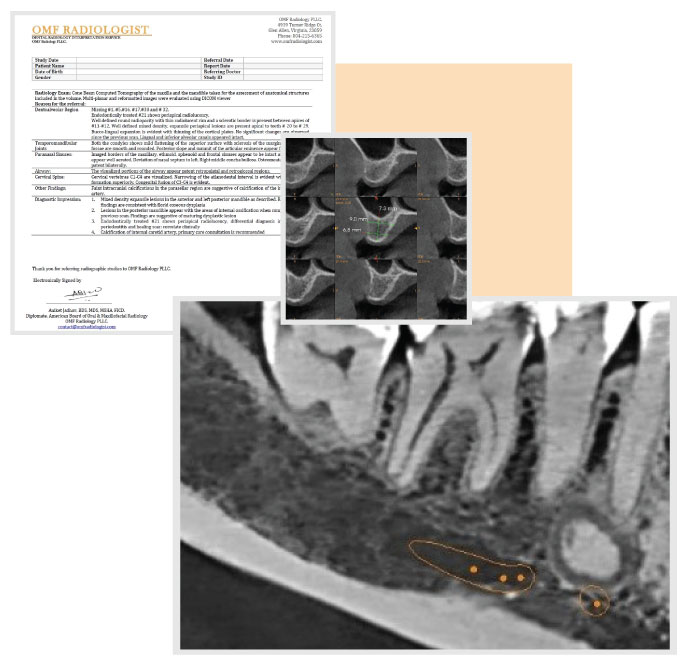

We provide concise and easy to understand CBCT interpretations that come with annotated key images. Regardless of your immediate treatment planning needs, the report provides a detailed and structured review of the anatomy, pathology and any incidental findings.

Our radiologist provides interpretation tailored towards the needs of dental speciality including annotated images on the radiology reports. Our reports are concise and aim to save you precious chair side time.